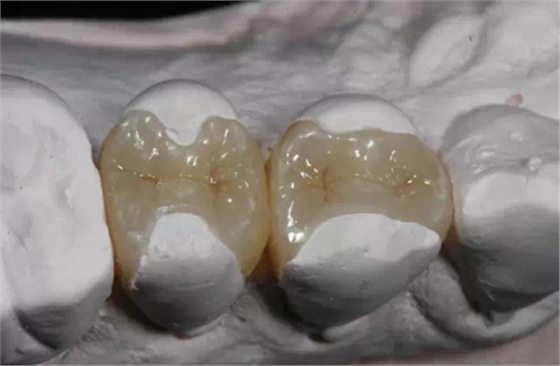

嵌體和傳統(tǒng)的補(bǔ)牙不同之處是,嵌體是在口外石膏模型上由專門的牙科技師制作出來的,然后再由臨床醫(yī)生將其戴入患者口內(nèi),最終粘固形成的。

嵌體的優(yōu)點(diǎn)就在于,它的整個(gè)的制作過程中完全避免了在口腔內(nèi)部操作的干擾因素。這就使得嵌體的制作比傳統(tǒng)的補(bǔ)牙要更精細(xì)。技師在制作嵌體的時(shí)候,會(huì)控制它與牙體的彌合程度,這樣就盡可能的避免了牙齒在日后的使用中再次出現(xiàn)齲壞。

嵌體的另一個(gè)優(yōu)點(diǎn)是,因?yàn)樗恼麄€(gè)制作過程是在口外完成的,所以它還可以很好的恢復(fù)原來牙齒的外形,恢復(fù)原來牙齒的咀嚼效率。而這一點(diǎn),是傳統(tǒng)補(bǔ)牙無論如何都無法比擬的